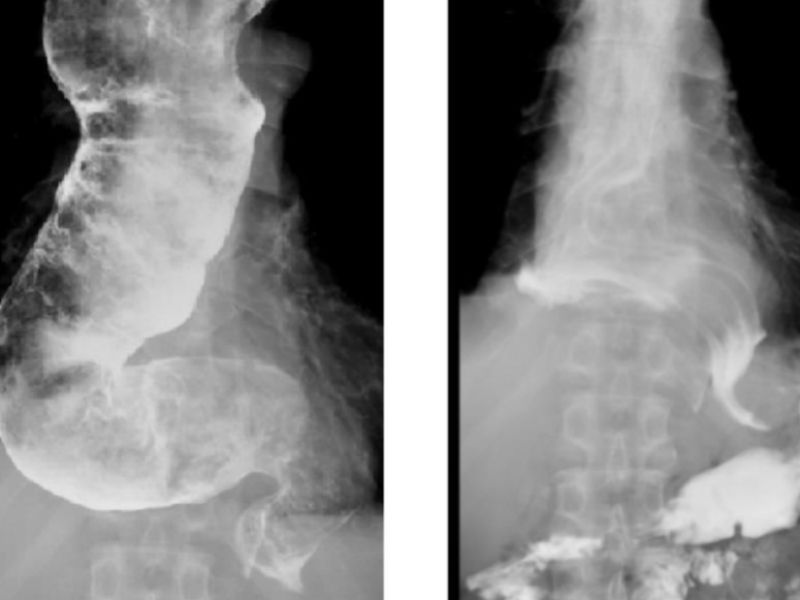

盧俊良說,食道遲緩不能症臨床症狀變化速度慢,且類似胃食道逆流,經常誤診,需要進行一系列完整的檢查方能確診。主要檢查工具包含上消化道內視鏡檢查,排除結構性異常(如食道腫瘤)、食道鋇劑攝影以及食道動力學檢查。其中以「食道動力學檢查」為確定診斷的黃金標準。